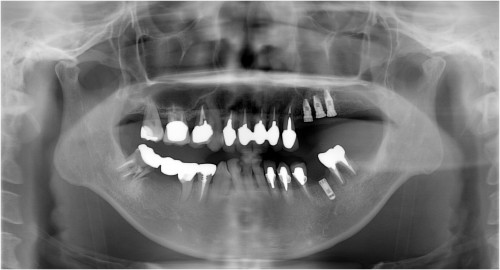

杉山5 左上56サイナスリフト後約3ヶ月